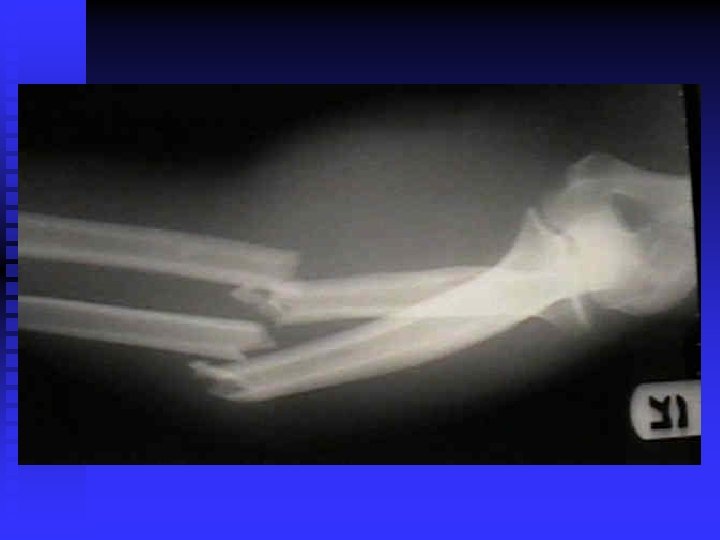

Forearm Fractures MOI: u Blow or fall on the outstretched arm n S&S: audible pop or crack, pain, swelling, and disability n TX: RICE, Splinting and casting n

Colles’ Fracture MOI: Fall on outstretched hand n S&S: Forward displacement of the radius, others are same as forearm fracture n TX: RICE, and casting n